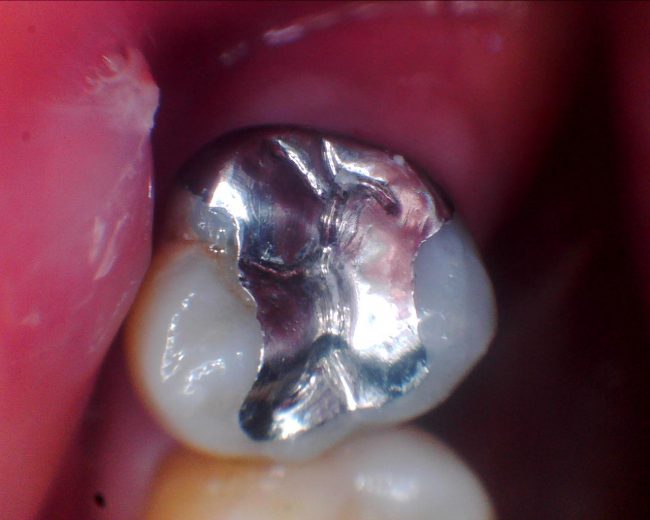

本日は、保険の銀歯の下が虫歯になって、やりなおしのケースです。

まずは治療前のレントゲン写真(デンタル)と、詰め物の様子です。

大きな金属(真っ白な部分)が入っています。レントゲンでは、少し黒い隙間があるようにも見えます。

お口の中では、やはり段差と隙間が見えますね。

もともとあまりぴったりしていないうえに、

多分最初はあった接着剤が溶け出してしまって隙間になったのだと思います。